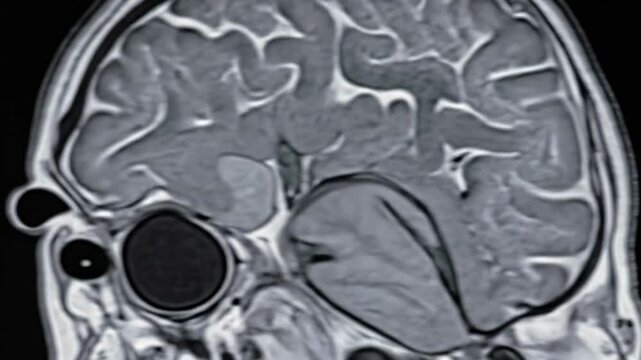

T2-weighted coronal plane fast spin echo MRI of the brain. Series description: Cor T2 FSE. Enlarged perivascular spaces are registered in the supratentorial white matter.

00:08

Progressive display of a human brain MRI showing coronal view slices for medical diagnosis and neurological study

Detailed coronal brain MRI scan highlighting cerebral structures, anatomical details, and white spots throughout the image on a black background.

00:07

Detailed coronal brain MRI scan showcases the brain's anatomy with contrasting gray and white matter and darker fluid filled spaces, a neuroimaging diagnostic tool.